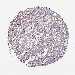

PANCREATIC CANCER - Protein expressioni

A mouse-over function shows sample information and annotation data. Click on an image to view it in a full screen mode. Samples can be filtered based on level of antibody staining by selecting one or several of the following categories: high, medium, low and not detected. The assay and annotation is described here.

Note that samples used for immunohistochemistry by the Human Protein Atlas do not correspond to samples in the TCGA dataset.

Antibody stainingi

Antibody staining in the annotated cell types in the current human tissue is reported as not detected, low, medium, or high, based on conventional immunohistochemistry profiling in selected tissues. This score is based on the combination of the staining intensity and fraction of stained cells.

Each image is clickable and will lead to virtual microscopy that enables deeper exploration of all samples and also displays staining intensity scores, fraction scores and subcellular localization as well as patient and tissue information for each sample.

Antibody HPA054975

Antibody CAB011464

Antibody CAB035990

Antibody CAB080407

Adenocarcinoma, NOS

Adenocarcinoma, metastatic, NOS